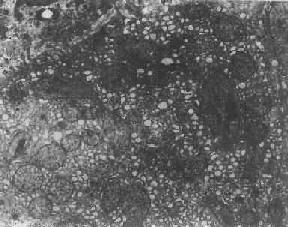

在生理状态下,随着细胞功能的升降,光面内质网(SER)的数量也呈现相应改变。但亦可出现完全相反的情况,例如在某些疾病(如淤胆)时,从形态结构上看,肝细胞光面内质网显著增生(图1-7),但其混合功能氧化酶的活性反而下降,这实际上是细胞衰竭的表现。

图1-7 肝细胞光面内质网增生伴轻度扩大